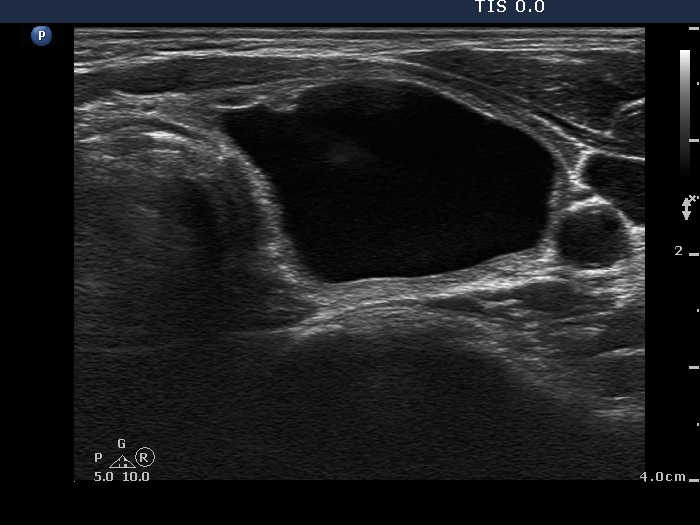

Ethanol sclerotherapy: other examples - Case 3: treatment of a gelatinous thyroid cyst

First session of therapy (ultrasonographic picture 1)

Right lobe, horizontal scan. The lesion a bit decreased in size.